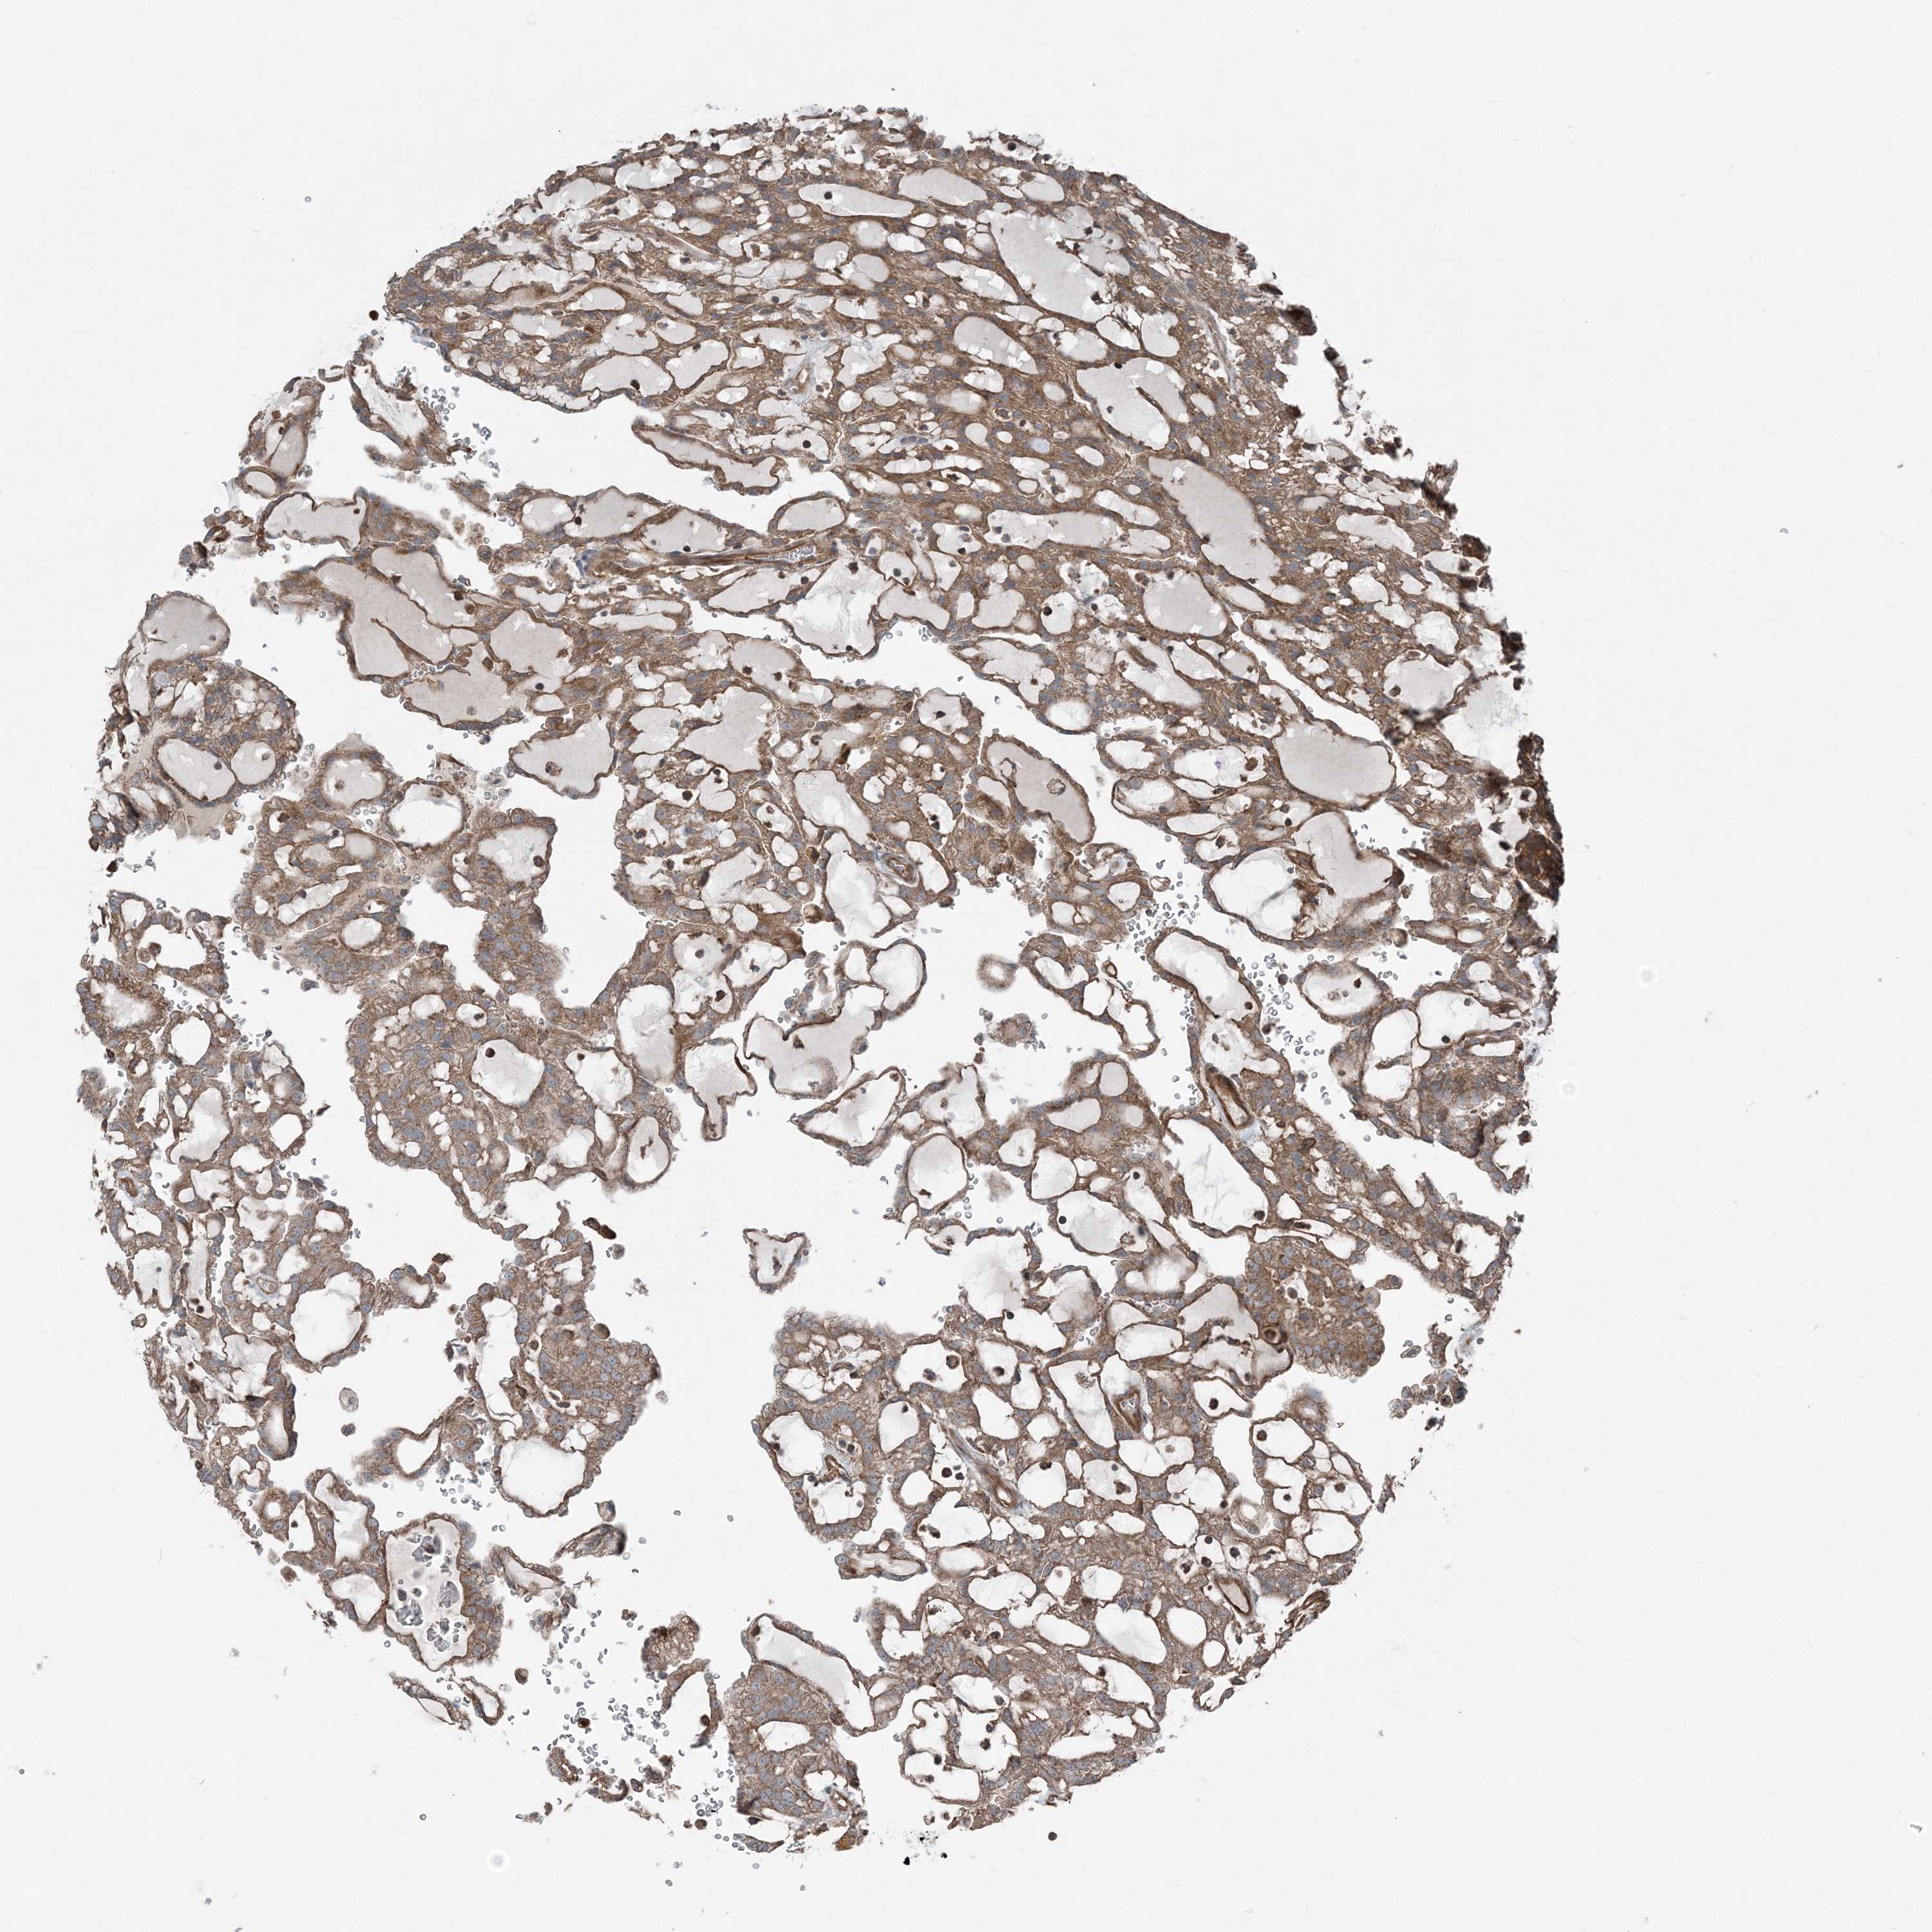

KIDNEY RENAL CLEAR CELL CARCINOMA (VALIDATION) - Interactive survival scatter ploti

The Survival Scatter plot shows the clinical status (i.e. dead or alive) for all individuals in the patient cohort, based on the same data that underlies the corresponding Kaplan-Meier plots. Patients that are alive at last time for follow-up are shown in blue and patients who have died during the study are shown in red.

The x-axis shows the expression levels (FPKM) of the investigated gene in the tumor tissue at the time of diagnosis. The y-axis shows the follow-up time after diagnosis (years). Both axes are complimented with kernel density curves demonstrating the data density over the axes. The top density plot shows the expression levels (FPKM) distribution among dead (red) and alive patients (blue). The right density plot shows the data density of the survived years of dead patients with high and low expression levels respectively, stratified using the cutoff indicated by the vertical dashed line through the Survival Scatter plot. This cutoff is automatically defined based on the FPKM cutoff that minimizes the p-score. The cutoff can be changed by dragging the vertical line or by entering a cutoff value in the square labeled "Current cut-off".

Under the Survival Scatter plot the p-score landscape (black curve; left axis) is shown together with dead median separation (red curve; right axis). Dead median separation is the difference in median mRNA expression between patients who have died with high and low expression, respectively. It is calculated as follows: median FPKM expression of dead patients with high expression - median FPKM expression of dead patients with low expression. This is intended to aid the user in visually exploring custom cutoffs and the associated p-scores and dead median separation.

Individual patient data is displayed and can be filtered by clicking on one or more of the category buttons on the top of the page. Categories describing expression level and patient information include: high, low, alive, dead, female, male and tumor stages. The scale of the x-axis can be toggled between linear and log-scale by clicking on the "x log" button. Mouse-over function shows TCGA ID, patient information and mRNA expression (FPKM) for each patient.

& Survival analysisi

Kaplan-Meier plots summarize results from analysis of correlation between mRNA expression level and patient survival. Patients were divided based on level of expression into one of the two groups "low" (under cut off) or "high" (over cut off). X-axis shows time for survival (years) and y-axis shows the probability of survival, where 1.0 corresponds to 100 percent.

KY is not prognostic in Kidney Renal Clear Cell Carcinoma (validation)

TCGA RNA samplesi

RNA-seq data is reported as average FPKM (number Fragments Per Kilobase of exon per Million reads), generated by the The Cancer Genome Atlas (TCGA) .

Normal distribution across the dataset is visualized with box plots, shown as median and 25th and 75th percentiles. Points are displayed as outliers if they are above or below 1.5 times the interquartile range. FPKM values of the individual samples are presented next to the box plot.

Average pTPM 0.3

Number of samples 100